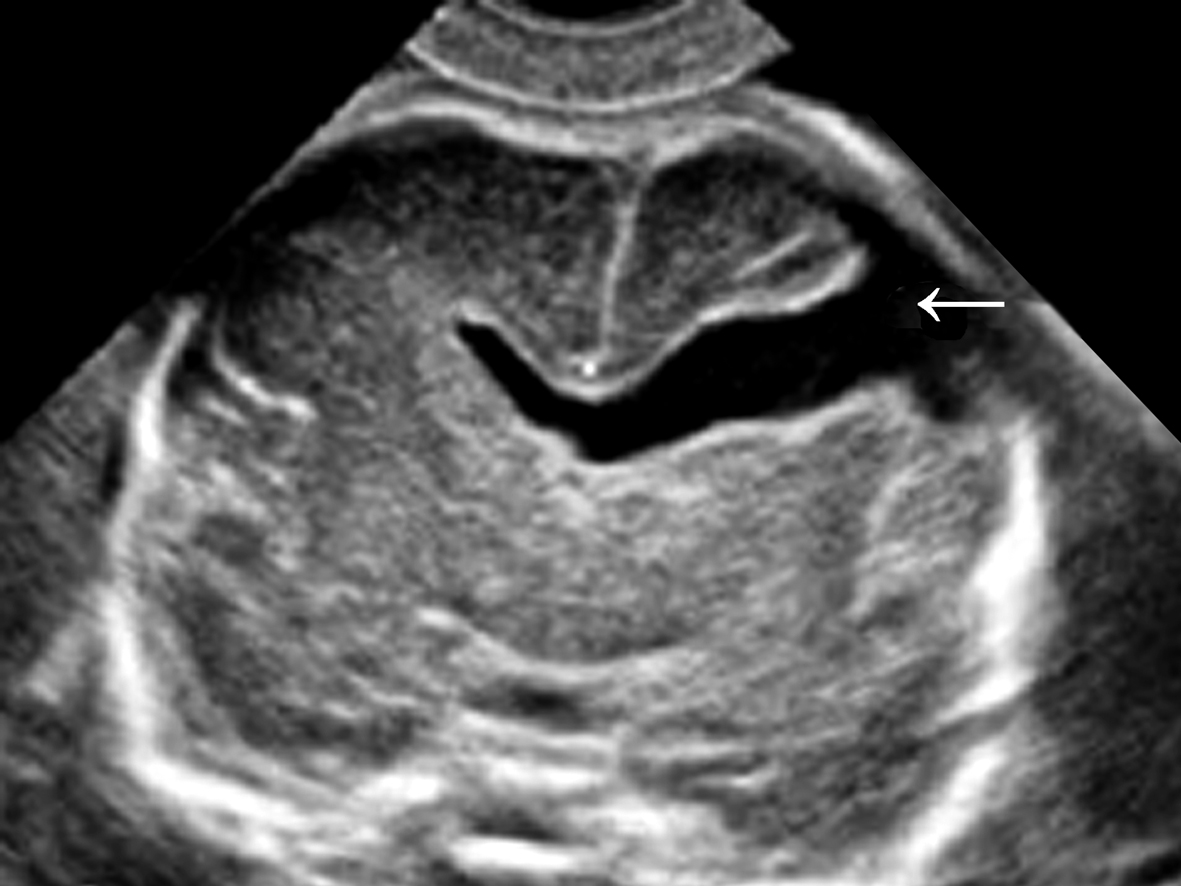

Ⅰ型超声容易漏诊,有时仅显示为脑实质内带状强回声(图1)。小的Ⅱ型脑裂畸形不仔细观察也容易漏诊,超声特有的“混响”伪像使得小裂隙模糊不清晰而漏诊。典型的Ⅱ型脑裂畸形表现为充满脑脊液的从大脑表面到脑室系统的裂隙(图2),裂开处的无回声与侧脑室相通,或者与蛛网膜下腔相通。裂开的表面有灰质覆盖,回声较强。可对称也可非对称,单侧或者双侧裂开。脑裂发生的部位不同,对颅内组织结构的影响不同,受影响的结构常常有透明隔不显示、脑室扩张、多小脑回畸形、胼胝体缺失等。三维超声检查可以通过连续的断面和三维重建追踪显示裂隙的走形和连接关系,有利于对Ⅱ型脑裂畸形的诊断。

图2Ⅱ型脑裂畸形声像图